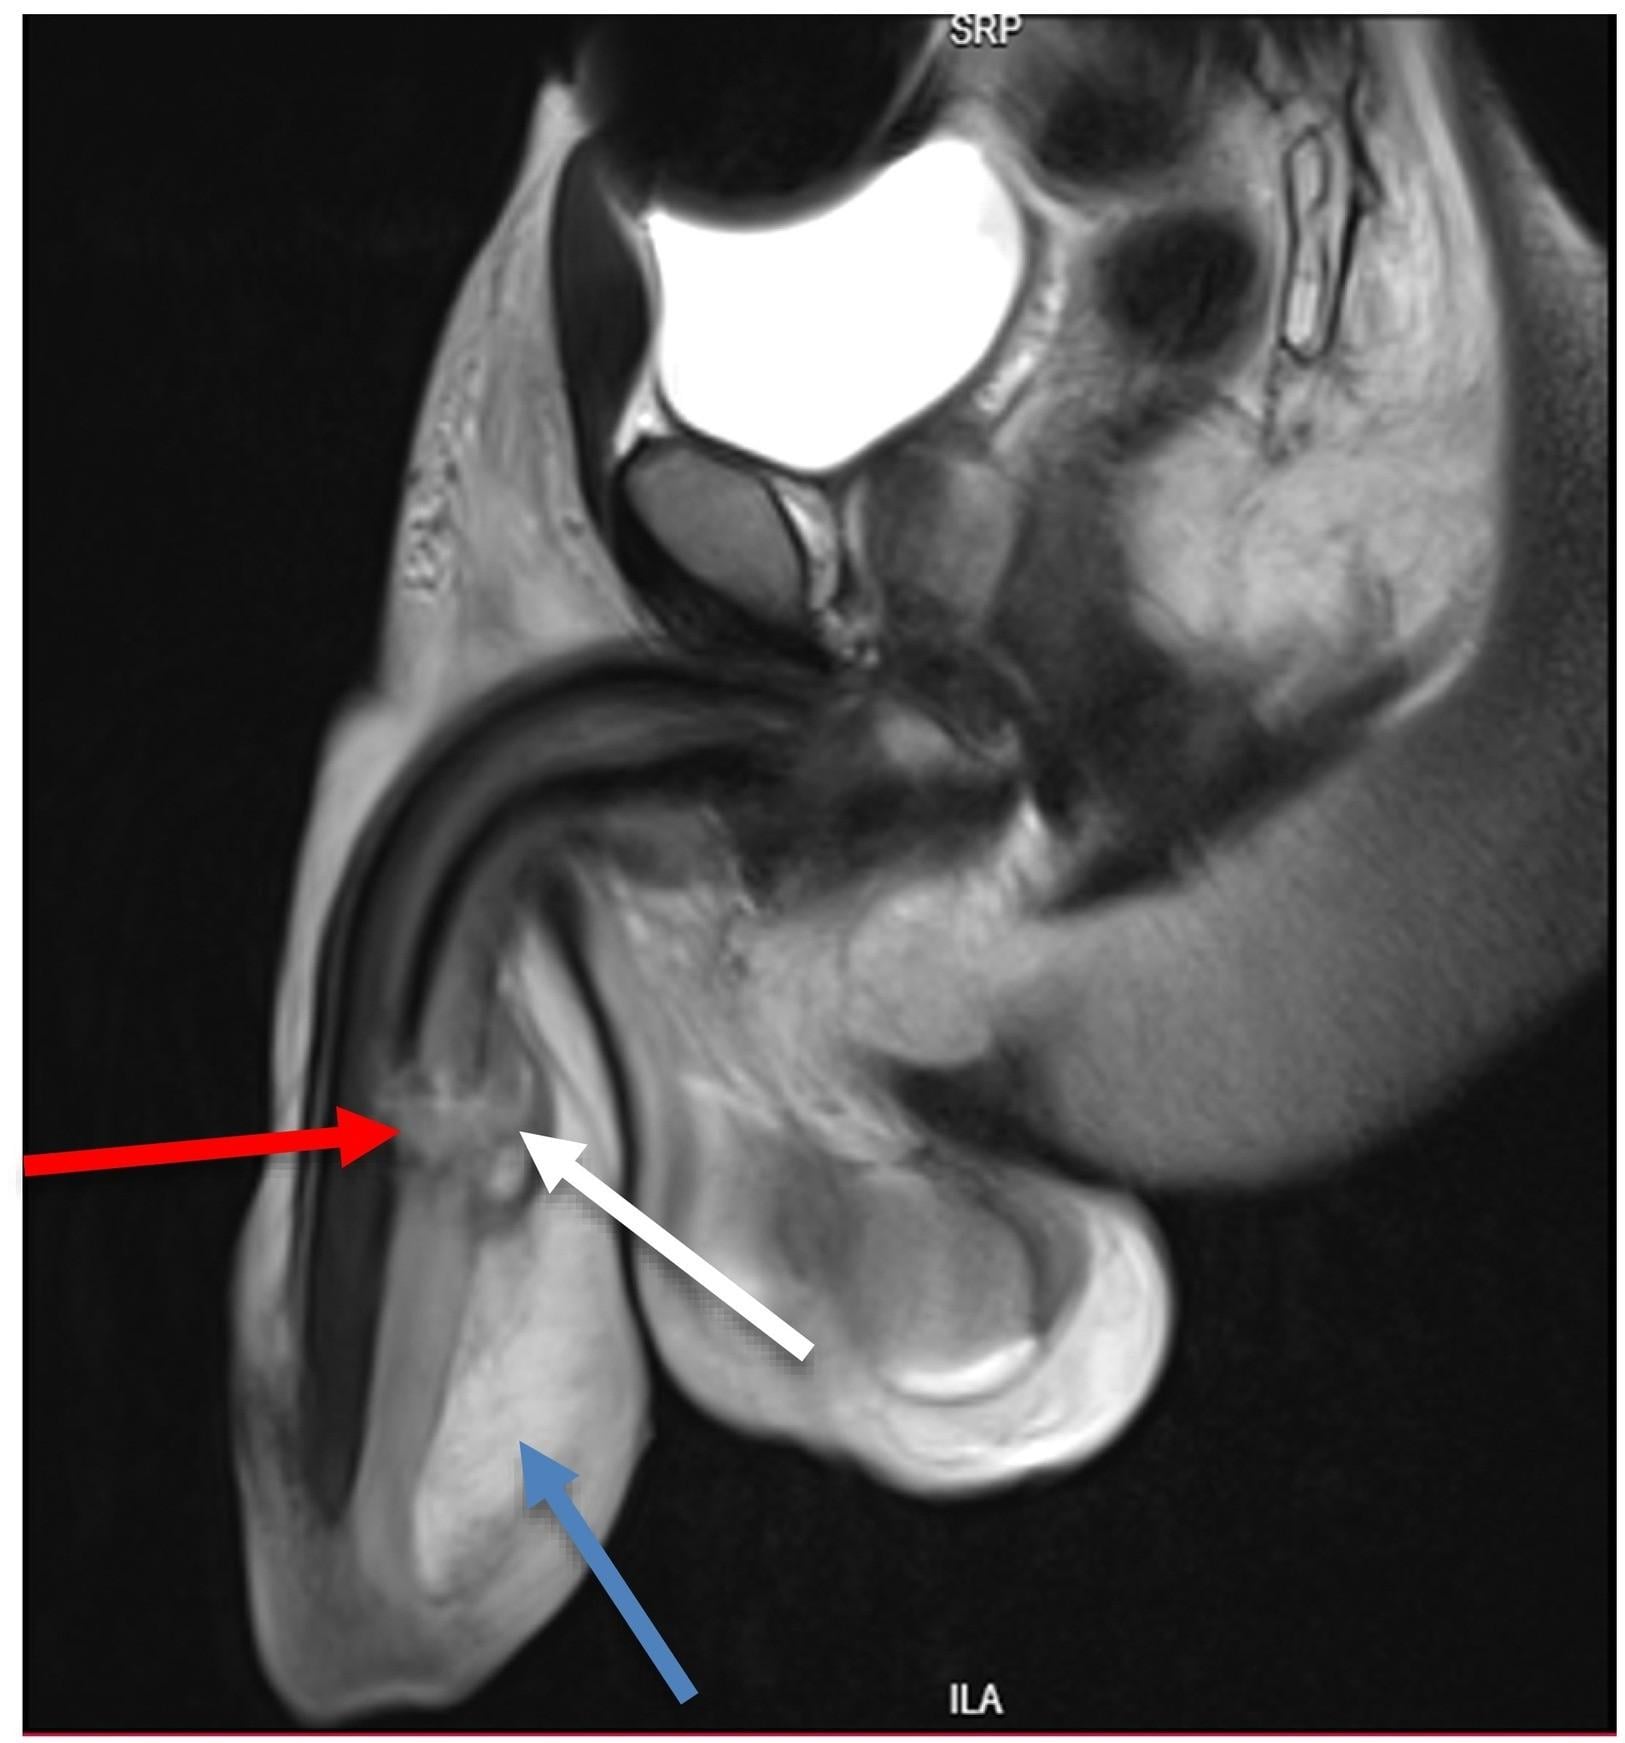

一名男子在行房時陰莖不慎撞斷,有三處受傷。(圖/翻攝自ScienceDirect)

據悉男子在抵達醫院時,陰莖已有腫脹流血的現象。醫師為他進行CT掃瞄後發現有三處斷裂,所幸在手術之後恢復良好,男子三天後就出院,六個月後回診時,他告訴醫師已恢復性生活,沒有受到影響。